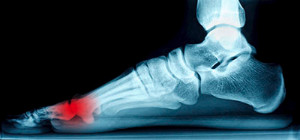

The bones that are located at the bottom of the big toe are referred to as sesamoid bones. They lie between the tendons of this toe, and pain and discomfort may be caused if inflammation occurs. This can happen as a result of overuse or if a sudden injury happens. Some of the symptoms that are associated with sesamoiditis often include pain while the big toe is pulled upward, and walking may be difficult when weight is placed on the foot. Once a diagnosis is performed, which includes having an X-ray or MRI taken, treatment can begin. It is helpful to wear shoes that provide adequate cushioning, in addition to wearing custom orthotics. If you feel you have sesamoiditis, it is suggested that you schedule a consultation with a podiatrist who can properly treat this condition.

Sesamoiditis is a condition of the foot that affects the ball of the foot. It is more common in younger people than it is in older people. It can also occur with people who have begun a new exercise program, since their bodies are adjusting to the new physical regimen. Pain may also be caused by the inflammation of tendons surrounding the bones. It is important to seek treatment in its early stages because if you ignore the pain, this condition can lead to more serious problems such as severe irritation and bone fractures.